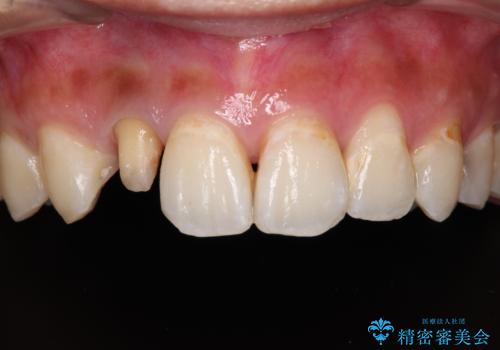

以前治療した前歯をきれいに治したい オールセラミッククラウン

- 根管治療はやり直さずに、ファイバーポストを使用した土台を植立して、オールセラミッククラウンにて補綴することとしました。

神経を取り除いた歯の変色は、クリーニングやホワイトニングでは改善できないため、オールセラミッククラウンなどによる補綴治療が必要となります。